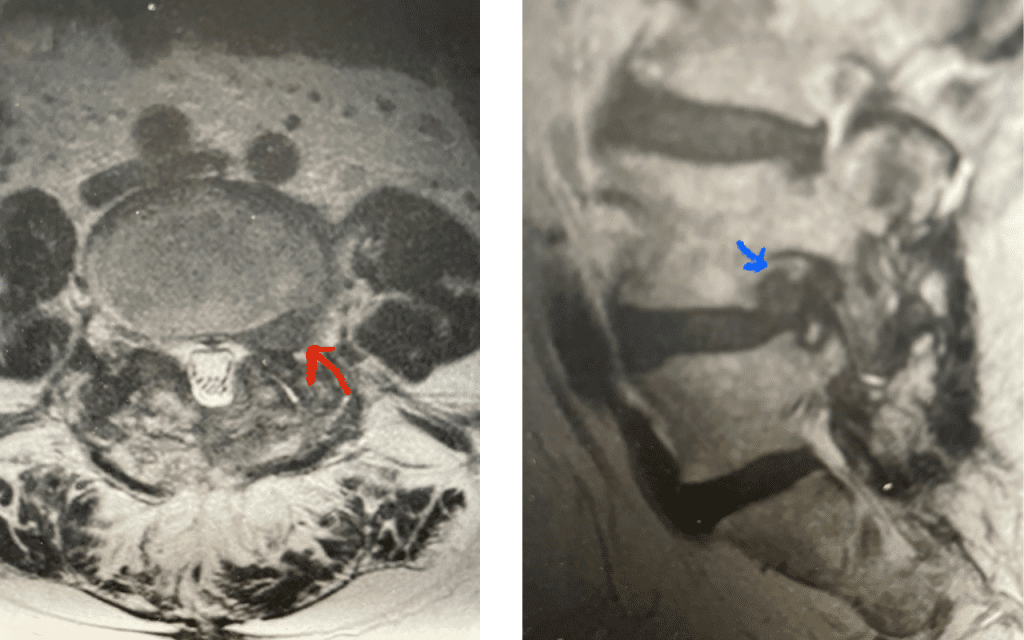

Fig 9: Axial and Sagittal T2-weighted lumbar MRI demonstrating left L4-5 far lateral disc herniation (red arrow). Notice how on the sagittal MRI the disc herniation fills the foramen and is superiorly oriented, compressing the left L4 nerve root against the L4 pedicle (blue arrow).

We had a recent flurry of lateral disc herniations. Another challenging case recently was a 76-year-old male who presented with 6 weeks of severe left anterior thigh pain, numbness, and weakness of his hip flexor and quadriceps, four years prior at L4-5 he had a removal of a large L4-5 synovial cyst on the right side of the canal and in situ fusion for which he had done very well. New imaging about a month prior revealed a new large far lateral disc herniation on the left side (Fig 9). The patient had mild spinal stenosis at this level and the cyst gone, but the disc on the left was extraforaminal at L4-5 compressing the left L4 nerve root. He had a trace spondylolisthesis. The patient underwent a series of epidurals with no improvement. Patient agreed to proceed with surgery. The laterality of the disc fragment made it amenable in our opinion for a lateral approach as to attempt a medial approach would be quite risky given the prior laminectomy and attendant scar formation which would increase risk for spinal fluid leak. The prior fusion mass was thin and incomplete and was removed easily with Kerrison punch. The main problem was the scarring in the intertransverse space and discerning the anatomy of the L4-5 facet complex. However, we remained in the “safe zone” and although the nerve was buried in scar tissue was not well identified, we were able to dissect enough to extract the disc fragment. This fragment was clearly pushing upward the scar tissue containing the L4 nerve root. We added an in-situ fusion with BMP because of the slight spondylolisthesis although we had to remove a minimal amount of bone in the safe zone for exposure. Fortunately, the patient had relief from his symptoms.